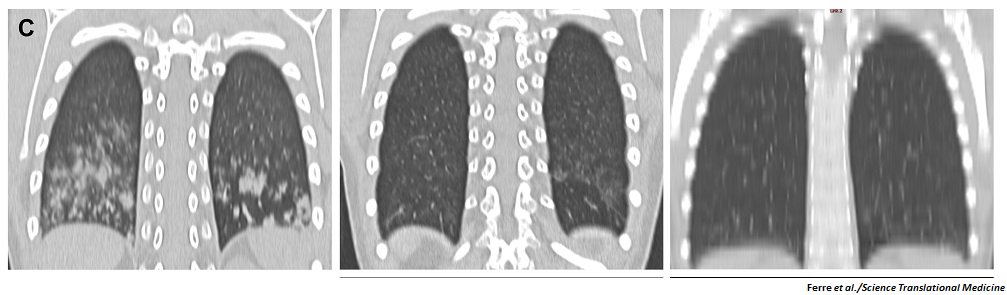

New research in @ScienceTM shows that targeting immune cell activity combats a serious lung-related complication often overlooked in patients with the autoimmune disease #APECED. fcld.ly/ulbexwp

42% of patients with #APECED have pneumonitis. If it is not treated early, it can lead to infections and severe bronchiectasis. Dr. Lionakis presents the results of a comprehensive study which showed the role of the accumulation of activated immune cells in the lung disease.

VHIR_'s tweet image. 42% of patients with #APECED have pneumonitis. If it is not treated early, it can lead to infections and severe bronchiectasis.

Dr. Lionakis presents the results of a comprehensive study which showed the role of the accumulation of activated immune cells in the lung disease.

From our NIH study team, check out this article highlighting the progress they’ve made diagnosing and treating #APECED #pneumonitis. ncbi.nlm.nih.gov/pmc/articles/P…

New research from the Lionakis lab reveals many patients with #APECED harbored previously-undiagnosed #pneumonitis, which was resolved with immunomodulatory drugs. @NIAIDNews fcld.ly/7t677o4

ScienceTM's tweet image. New research from the Lionakis lab reveals many patients with #APECED harbored previously-undiagnosed #pneumonitis, which was resolved with immunomodulatory drugs. @NIAIDNews fcld.ly/7t677o4